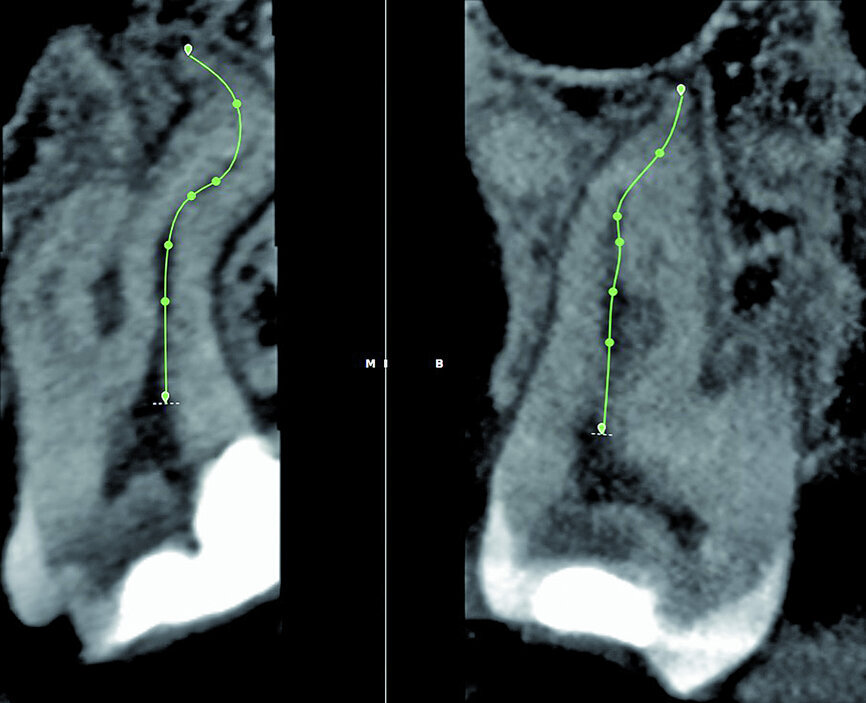

Fig. 7: The 3D Endo Software proposal of the canal anatomy that can be corrected by the operator, according to the canal configuration viewed in different planes in the software. In most cases, the proposal is very good but in this case it was not accurate because of the multi-planar canal anatomy.

Fig. 8: Corrections made for the palatal root canal according to the canal configuration that can be viewed in different planes in the software.

Fig. 9: Corrections made for the mesiobuccal root canal according to the canal configuration that can be viewed in different planes in the software.

Fig. 10: Corrections made for the distobuccal root canal according to the canal configuration that can be viewed in different planes in the software.

With the fourth step, ‘3D Canal Anatomy’, the software made a proposal of the canal anatomy (Fig. 7), but the operator can make corrections according to the canal configuration that can be viewed in different planes in the software. Figures 8 to 10 show the mapping of the palatal, mesiobuccal, and distobuccal root canal systems.